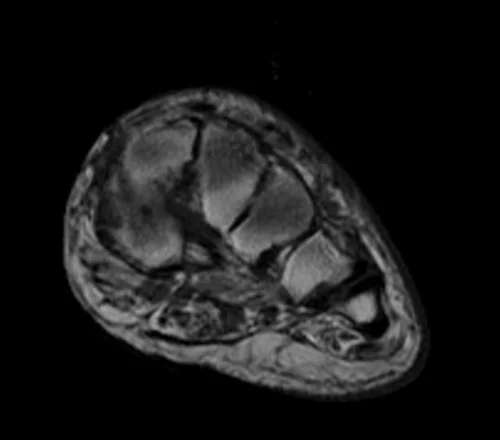

MRI FOOT AXIAL T1 IMAGE 3 - MRI